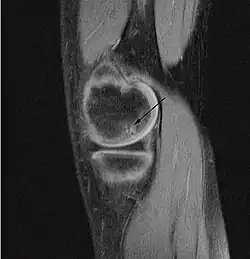

Magnetische kernspinresonantie (MRI) is een bruikbare techniek om de verergering van OCD-beschadigingen in de gaten te houden, om het gewrichtsoppervlak te beoordelen en om normaal botweefsel te kunnen onderscheiden van OCD doordat bot- en kraakbeenoedeem zichtbaar worden op de plek van de ongelijkmatigheden. Een MRI geeft informatie over de toestand van het gewrichtskraakbeen, het bot onder het kraakbeen, oedeem, breuken, vochtophoping, de toestand van het gewrichtsoppervlak en de verplaatsing van losse fragmenten. Bij actieve beschadigingen is er een lage signaalintensiteit op een T1-gewogen opname en een hoge signaalintensiteit op een T2-gewogen opname. Dit duidt op een onstabiele beschadiging of recente microbreuken. MRI en artroscopie geven samenhangende resultaten. Uit röntgenopnames zijn minder snel conclusies te trekken dan uit MRI-resultaten.